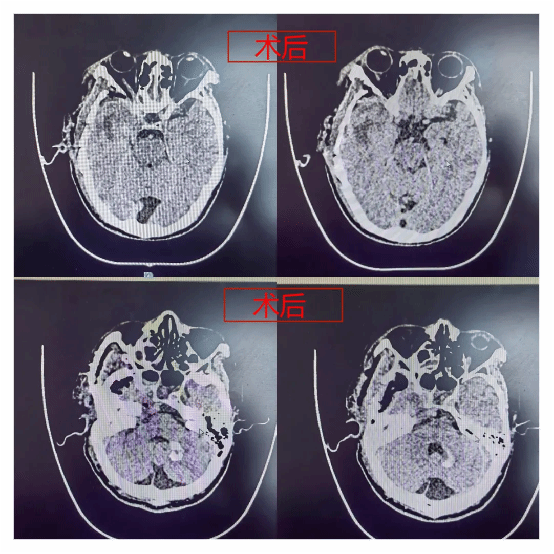

术中,在面对颈内动脉及脑干附着面时郭清保主任谨慎剥离肿物,并时刻关注患者生命体征变化,手术顺利完成。患者术后正常苏醒,神经功能完好保留。

一周后,薛大爷已能下地行走,郭主任再三叮嘱薛大爷要做好定期复查,患者及家属对科室医护的全力照护向郭清保主任及其团队赠送锦旗以表衷心感谢。